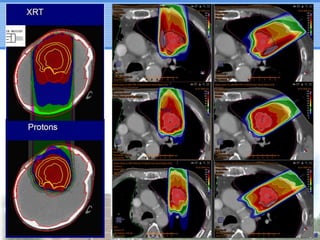

PBT for StageIII NSCLC • Need for dose escalation: – RTOG trials (X-rays): 8311 (+) and 0617 (-) • Few dosimetric comparison studies: – Advantage of PBT over X-rays seems more significant in stage III than stage I • Recent on-going trials of high-dose PBT with concurrent chemotherapy – Safe and effective

PBT for IIINSCLC • Need for dose escalation: – RTOG trials (X-rays): 8311 (+) and 0617 (-) • Few dosimetric comparison studies: – Advantage of PBT over X-rays seems more significant in stage III than stage I • Recent on-going trials of high-dose PBT with concurrent chemotherapy – Safe and effective

Summary • PBT cangive excellent dose distribution using less ports (Bragg peak) • PBT maybe more widely applicable than SABR even with pulmonary comorbidity and difficult tumor location in stage I • PBT may save more normal tissue in stage III than in stage I • Pencil beam scanning seems promising • Dose-escalated PBT with concurrent CTx may be safe and effective